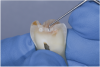

When such a fissure that does not present an explorer “stick” is explored with a small-diameter bur in a procedure called a “caries biopsy,” caries is nearly always found in areas with an underlying discoloration or shadow.9 Any caries discovered can then be excavated where needed. The susceptibility of a fissure to explorer probing for a “stick” is, therefore, irrelevant to the diagnosis of caries within the fissure (Figure 3 and Figure 4).

Fig 3. Clinical appearance with no perceptible “stick” with an explorer on a patient with tetracycline-stained teeth.

Figure 3

Fig 4. Extent of caries upon exploration was very broad, undermining cusps.

Figure 4